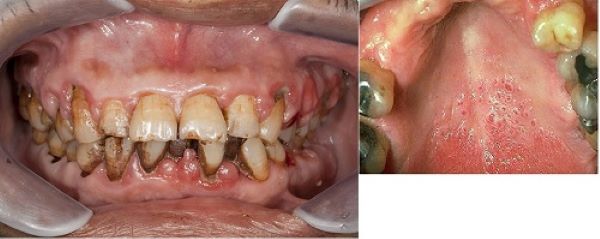

Khói thuốc làm tê liệt và thậm chí tiêu diệt các vi nhung mao (tế bào lông chuyển) trong phổi. Khi không có các nhung mao này, người hút thuốc rất nhạy cảm với COVID-19.